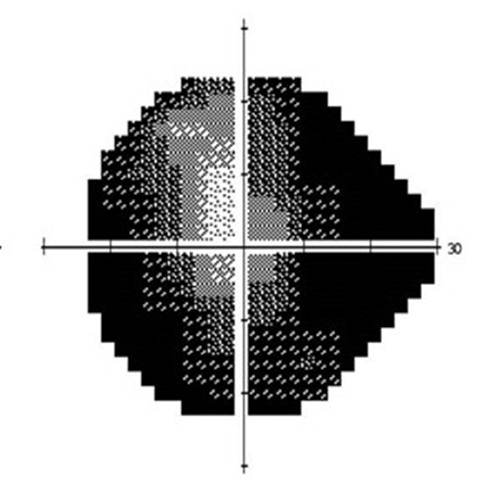

(图左:视力正常人士的视野;图右:晚期青光眼患者的视野)